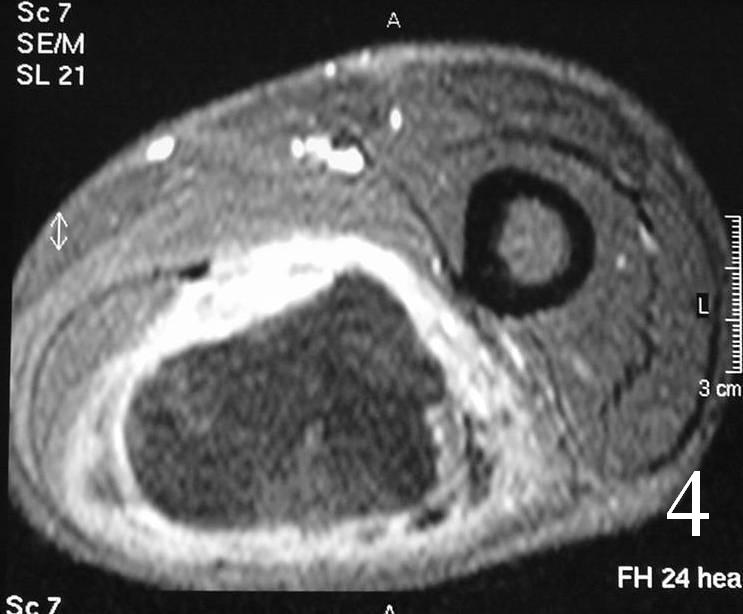

- With gadolinium (Fig. 4, 5)

- Reverse target post-contrast

- Increased gadolinium uptake——->unlike peripheral nerve sheath tumor (PNST)

MRI of the thigh, showing a heterogeneous soft tissue lesion in the posterior compartment of the thigh on axial (Fig. 2) and coronal (Fig. 3) T1W images. The addition of gadolinium contrast shows enhancement in the periphery of the mass with necrosis and hemorrhage in the center of the mass typical of a high grade sarcoma (Fig. 4 and 5)